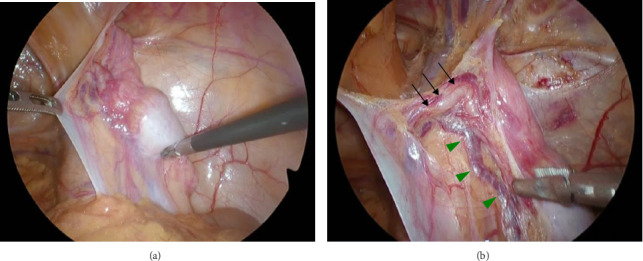

背景:隐睾是新生儿男性最常见的先天性异常之一,大多数在婴儿期诊断并在青春期前手术治疗。在某些情况下,隐睾是在成人腹股沟疝修补时偶然发现的,需要在手术时进行适当的处理。病例介绍:病例1:一名58岁男性因左侧嵌顿疝接受紧急腹腔镜手术。术中发现一例M2型腹股沟斜疝伴精索网膜绞窄。尽管试图用手把睾丸拉下来,但它没有下降到阴囊内,这导致了隐睾症的诊断。切除精索,放置3D网片覆盖疝缺损。病例2:一名33岁的努南综合征患者,表现为右腹股沟局部疼痛和肿胀。腹腔镜检查发现三层腹股沟斜疝,并发现腹腔内睾丸。发现睾丸和精管在腹腔内终止,确认隐睾的诊断。行睾丸切开术,将睾丸皮下固定于阴囊内,并用3D补片修复疝。结论:隐睾合并腹股沟疝行补片修补术的安全性已有文献报道。在术前因疼痛难以触诊的情况下,术中牵拉睾丸有助于区分隐睾症和收缩性睾丸。此外,睾丸切除术可作为一种临时措施,必要时可考虑分期切除。

Background: Cryptorchidism is one of the most common congenital anomalies in newborn males, with the majority diagnosed in infancy and treated surgically before puberty. In some cases, cryptorchid testes are discovered incidentally during inguinal hernia repair in adults, requiring appropriate management at the time of surgery. Case Presentation: Case 1: A 58-year-old male underwent emergency laparoscopic surgery for a left incarcerated hernia. Intraoperatively, an M2 indirect inguinal hernia with omental strangulation of the spermatic cord was identified. Despite attempts to pull the testis down manually, it did not descend into the scrotum, leading to the diagnosis of cryptorchidism. The spermatic cord was excised and a 3D mesh was placed to cover the hernia defect. Case 2: A 33-year-old man with Noonan syndrome presented with localized pain and swelling in the right groin. Laparoscopy revealed an indirect L3 inguinal hernia and incidentally an intra-abdominal testis was found. The testis and spermatic vessels were found to terminate intra-abdominally, confirming the diagnosis of cryptorchidism. An orchiopexy was performed to secure the testis subcutaneously in the scrotum and the hernia was repaired with a 3D mesh. Conclusion: The safety of mesh-based hernia repair in cases of cryptorchidism with concomitant inguinal hernia has been previously reported. In cases where preoperative palpation is difficult due to pain, intraoperative traction of the testis may help differentiate between cryptorchidism and retractile testis. In addition, orchiopexy may serve as a temporary measure, with consideration of staged orchiectomy if necessary.